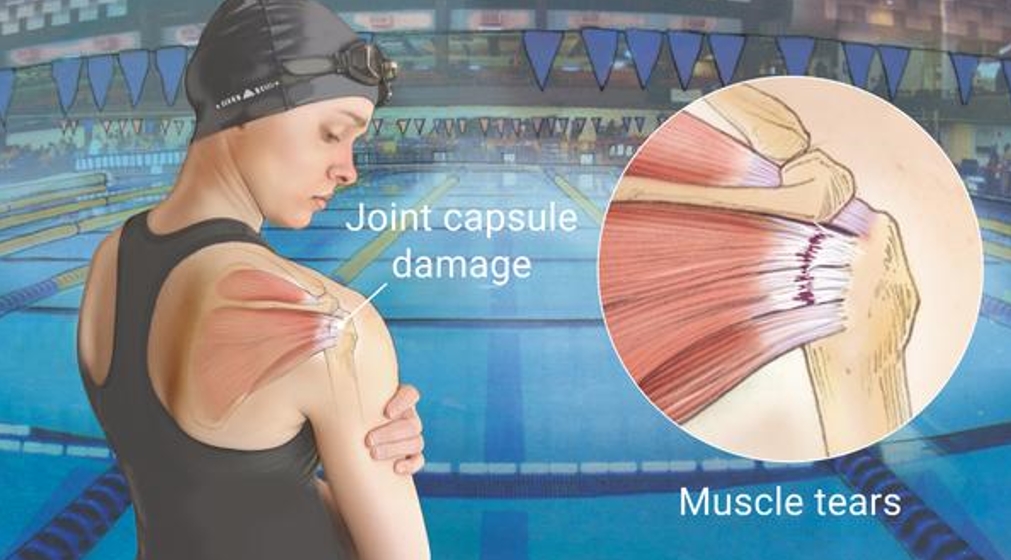

2. 重複性動作:長期進行重複性的肩膀動作 (例如網球、游泳) 或需要大量提舉的工作,會對肩袖造成壓力並導致損傷。